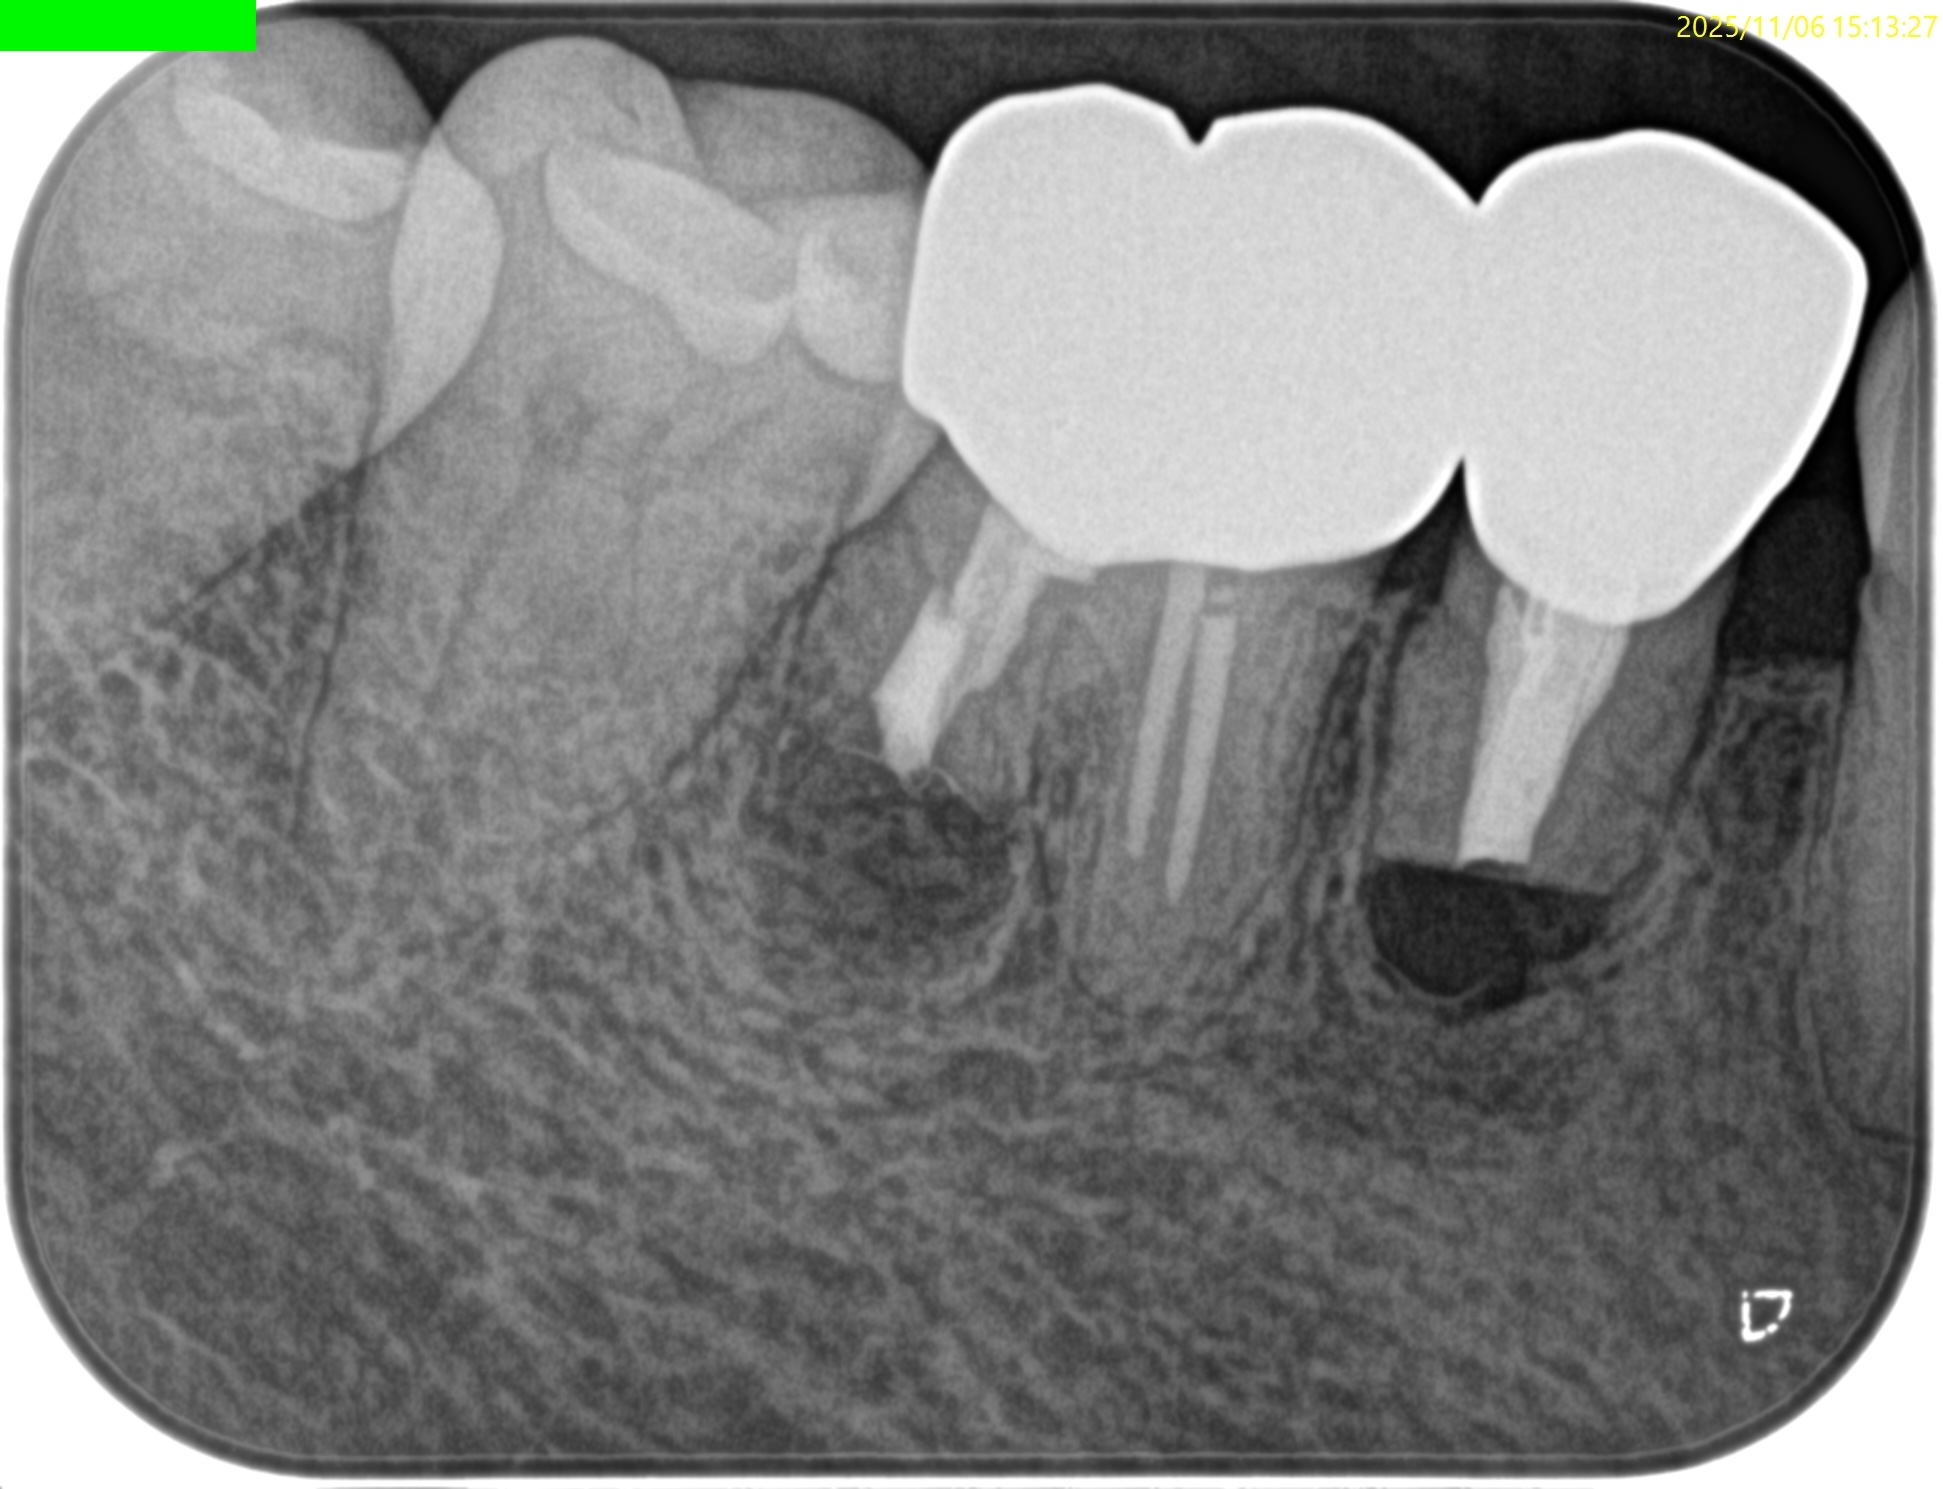

PAを撮影した。

PA, CBCTを撮影した。